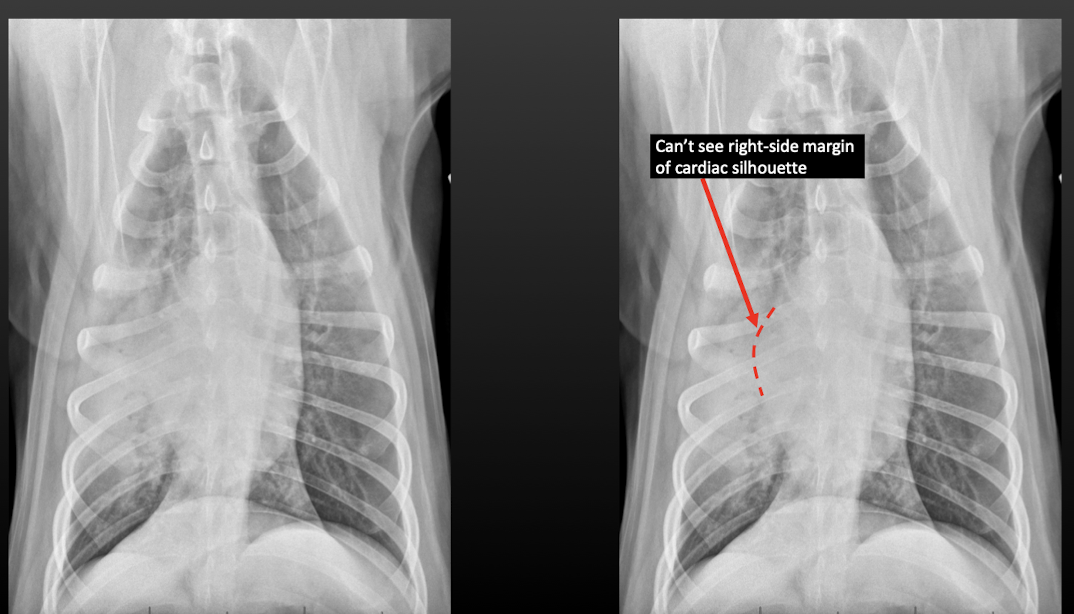

Q

What is the appearance of border effacement?

A

Lose visibility of margins of cardiac silhouette, diaphragm, etc.

Lung Pattern?

Alveolar

Border effacement

How well did you know this?